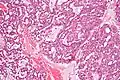

Low magnification micrograph of a polymorphous low-grade adenocarcinoma, showing the typical variation of architectural arrangement. H&E stain.

PLGAs consist of a monomorphous cell population that has a varied histologic morphology.

Microscopically, its histology can be confused with an adenoid cystic carcinoma and a pleomorphic adenoma.